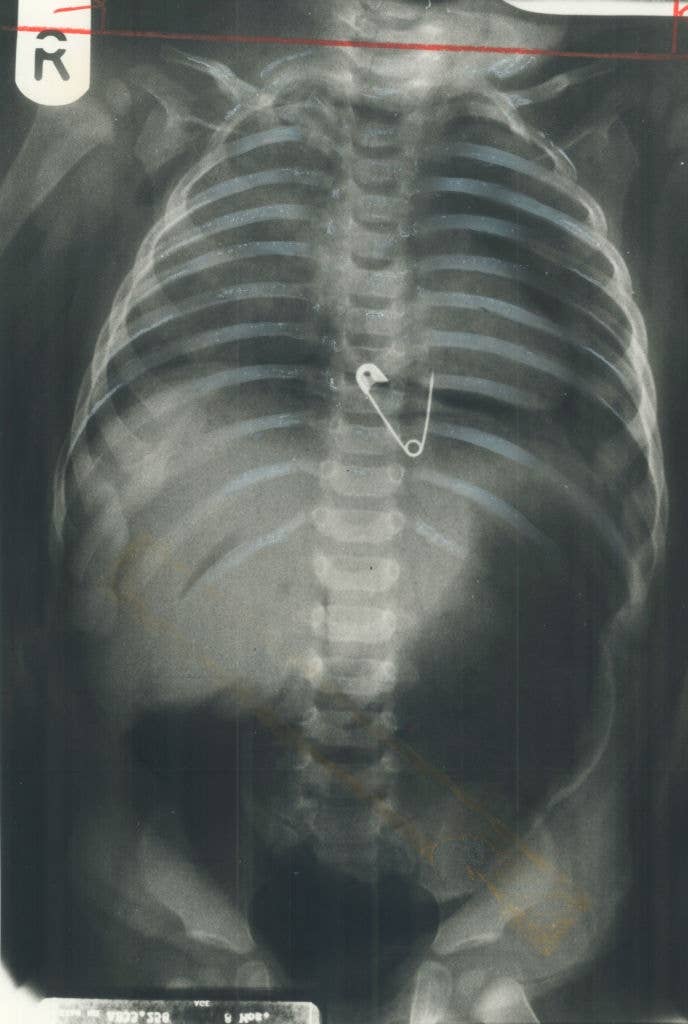

Be honest, is it actually wilder than Grey’s Anatomy? πŸ‘€